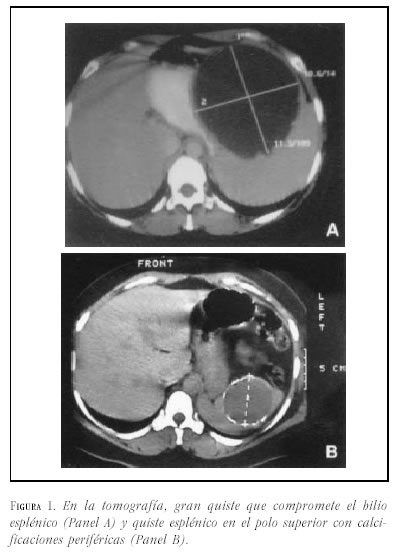

Caso 1. Mujer de 29 años a quien se le detecta, el décimo día de posoperatorio de cesárea, una masa en hipocondrio izquierdo. Presenta antecedente de abortos recurrentes con estudio de anticuerpos antifosfolípidos negativo. En la ecografía de abdomen se encuentra un bazo de 17.5 cm con quiste de 10 cm de diámetro. La tomografía de abdomen (figura 1A) muestra un bazo de 18 cm y lesión quística de 11X10 cm. Se practica laparotomía (figura 2A) y se realiza esplenectomía total donde se encuentra el bazo de 1420 g con gran quiste de 15X13 cm, el cual compromete el hilio (figura 3A). En el posoperatorio presenta episodio de obstrucción intestinal que requiere laparotomía. Por nuevo episodio de obstrucción intestinal parcial a los 16 meses, se realiza tránsito intestinal cuyo resultado es normal y tomografía de abdomen encontrándose alteración en estructuras vasculares portales y suprahepáticas. La resonancia magnética de hígado muestra trombosis de la porta y esplénica, obstrucción de venas hepáticas y lesiones nodulares hepáticas que pueden corresponder a proceso infiltrativo. Se realiza laparoscopia donde se evidencia ascitis e hígado firme con nódulos. Biopsia reporta cirrosis. La paciente es remitida para su evaluación para trasplante hepático, el cual es practicado. A las 9 horas del trasplante se diagnostica insuficiencia hepática y se encuentra hígado hipertenso mal perfundido con trombosis vascular. Se realiza reimplante. Fallece en el posoperatorio.

Caso 2. Mujer de 36 años quien consulta al servicio de urgencias por epigastralgia. No presenta antecedentes de importancia. El examen físico es normal. Se realiza esofagogastroduodenoscopia y se diagnostica hernia hiatal tipo I. En la ecografía de abdomen se encuentra un bazo de 11 cm y quiste esplénico de 6X5 cm. La tomografía de abdomen (figura 1B) confirma la presencia de un quiste de este tamaño que compromete el polo superior del bazo. Se le practica laparotomía (figura 2B) con esplentectomía parcial (figura 3B). La evolución posoperatoria es buena.